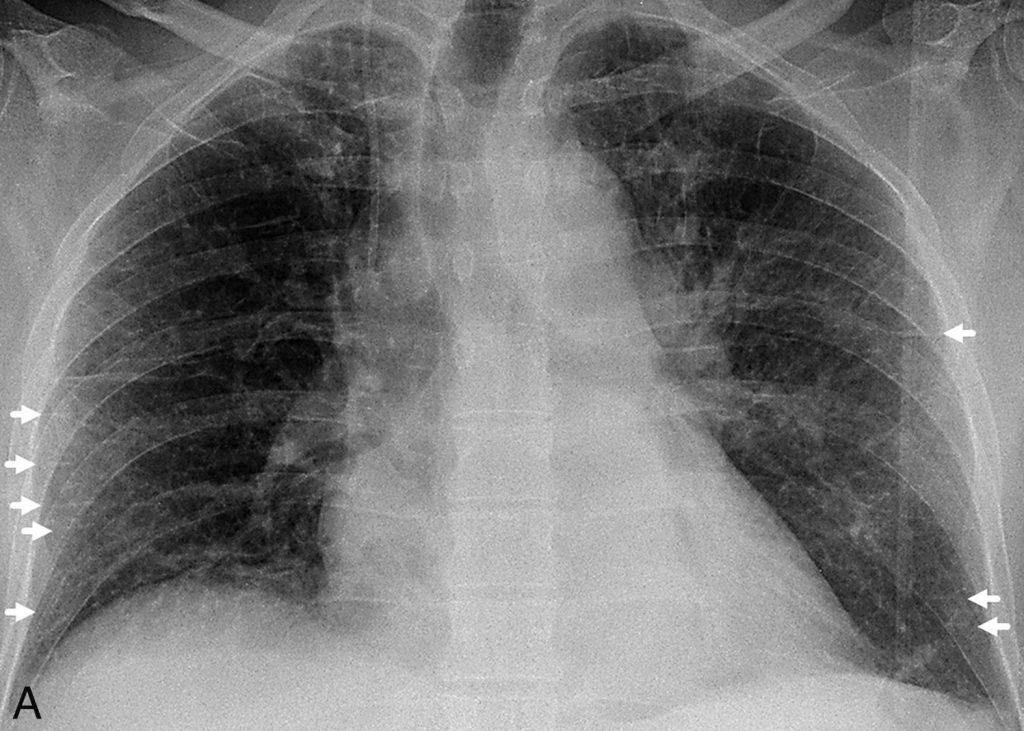

En cas d’OAP, la radiographie montre une cardiomégalie, un épanchement pleural souvent bilatéral et symétrique, une redistribution vasculaire vers les sommets et des signes d’atteinte interstitielle (lignes de Kerley de type B) ou alvéolaire (opacités alvéolaires bilatérales à prédominance périhilaire) (figure 93.1). Dans l’œdème pulmonaire lésionnel, la silhouette cardiaque est généralement normale et les opacités pulmonaires souvent plus périphériques.

Fig. 93.1. Radiographie thoracique.

(A) Radiographie de thorax de face en position debout. Œdème pulmonaire cardiogénique associant un élargissement de la silhouette cardiaque et des lignes de Kerley de type B (flèches). (B) Radiographie de thorax de face en position couchée (autre patient). Œdème pulmonaire cardiogénique sévère associant un élargissement de la silhouette cardiaque, un épanchement pleural bilatéral (opacités basales à limites floues, effacement des culs-de-sac, épaississement de la petite scissure) et des opacités alvéolo-interstitielles bilatérales à prédominance péri-hilaire.

Source : CERF, CNEBMN, 2022.